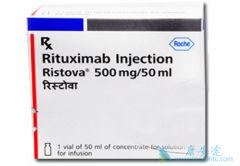

为什么 美罗华 (Ristova)需要缓慢静滴?Ristova是人鼠嵌合型单抗,从理论上有发生HAMA的可能,但是目前我们还没有观察到。制剂分100mg和500mg两种,使用前静推氢化考的松100mg,预防过敏反应。先使用100mg,缓慢静滴,如无明显反应,再开封500mg,整个 ...

美罗华 (Rituximab)什么时间用效果更好?一般和基于CHOP方案的化疗比较多见。美罗华 d0+CHOP,即R-CHOP方案是目前老年人低度恶性淋巴瘤、惰性淋巴瘤治疗的一线方案,当然在经济条件允许的条件下。美罗华使用的时机,目前研究较多。有认为化疗前用, ...